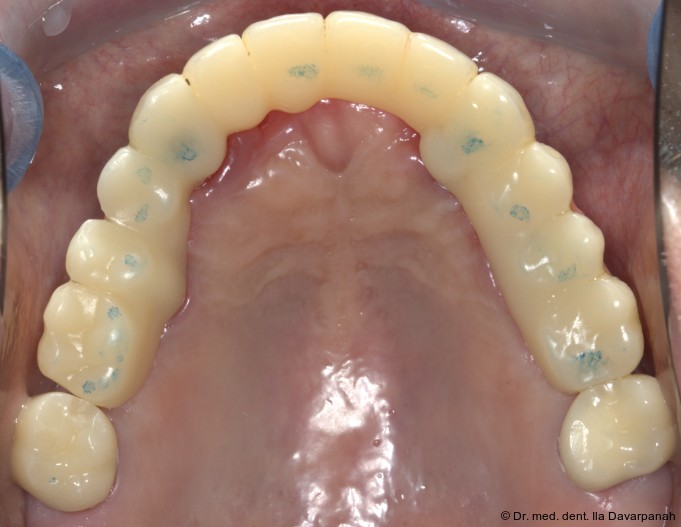

Auf Basis des digitalen Mock-ups wurden die Zirkonoxid-Primärkappen, galvanisch hergestellten Sekundärkappen sowie das NEM-Tertiärgerüst laborseitig gefertigt (Abb. 13+14). Die intraorale Verklebung der Sekundärkappen mit dem Tertiärgerüst erfolgte spannungsfrei im Mund (Abb. 15–17).

Eingliederung der Reise- und Definitivprothese

Nach Verkleben der sekundären Galvanokappen mit dem Tertiärgerüst verbleiben die Primärzirkonkappen im Mund. Um dem Patienten auf Basis dieser Pfeiler eine Interimsversorgung geben zu können, wird eine sogenannte Reiseprothese mit der Ästhetik und Funktion der finalen Versorgung hergestellt, welche auch als Referenz hierfür dient (Abb. 18+19).

Die definitive Prothese konnte im dritten Behandlungstermin problemlos eingegliedert werden. Es waren lediglich minimale okklusale Anpassungen erforderlich (Abb. 20–24).